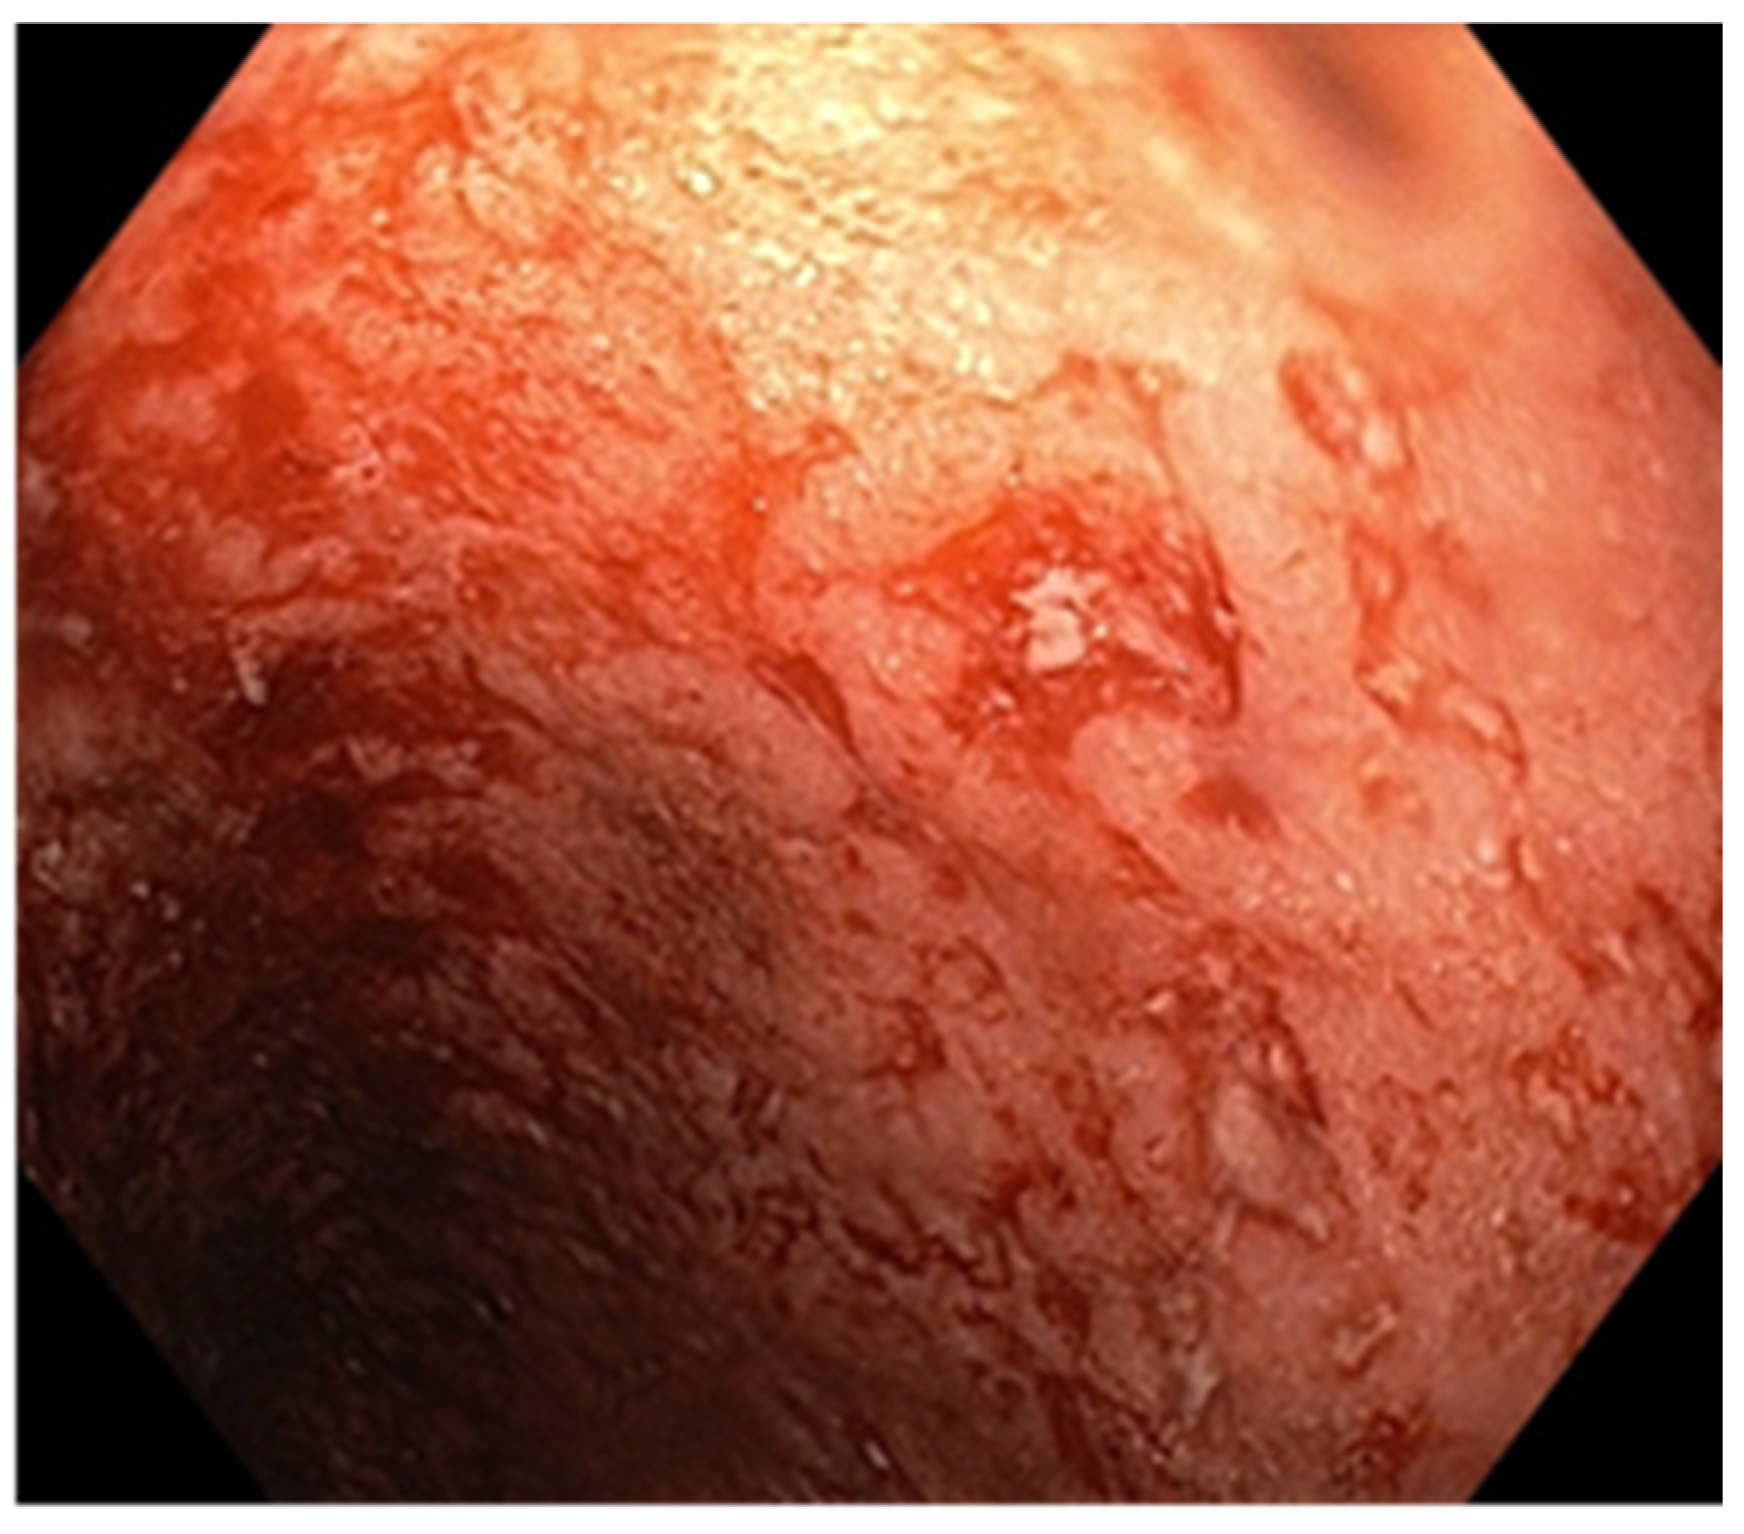

Figure 4.

Endoscopic aspect—small and deep ulcers.

A 25-year-old man with a history of recurrent chronic pancolitis and backwash ileitis with one episode of exacerbation in the past three months, on a combined treatment of Adalimumab at a dose of 40 mg every two weeks, Azathioprine at a dose of 100 mg/day, and Mesalazine at a dose of 3 g/day, presented with diarrheal stools (seven to eight per day) containing mucus and blood, including nocturnal episodes, and weight loss (BMI 19). Laboratory tests revealed normochromic and normocytic anemia, thrombocytosis, dyselectrolotemia, hypoproteinemia with hypoalbuminemia, elevated ferritin levels, and a very high CRP. The fecal calprotectin was measured at 5400 µg/g. Anti-adalimumab antibodies were detected with a value of 7 (<10 AU/mL) and an Adalimumab trough level of 15 µg/mL. To determine the etiology of the current exacerbation, we performed stool bacterial and mycological examinations, as well as serology to identify any bacterial or viral infection. An increase in the HCMV IgG antibody titer to 480 AU/mL from an initial value of 190 AU/mL was observed, although HCMV IgM was negative. Given the high suspicion of superinfection with CMV, we performed an HCMV DNA test from the blood and obtained a result of 2820 IU/mL. For confirmation, we performed an ileocolonoscopy, which revealed continuous lesions, extending from the rectum to the terminal ileum. These lesions were characterized by erosions, small but deep ulcers, marked mucosal friability, and a lack of a vascular pattern, corresponding to Mayo 10p (Figure 4). Multiple biopsies were taken during the procedure, including from the edges and bottom of the ulcers. The histopathological examination confirmed our suspicion of diffuse chronic inflammation, with architectural distortions. Notably, we observed marked activity with crypt abscesses and ulcerations with granulation tissue formation. More than five viral inclusions were identified in the endothelial cells on multiple fragments, which tested positive for HCMV immunostaining (Figure 5). Due to the pandemic situation and the patient’s stable condition, we decided to discharge the patient and initiate treatment with Valganciclovir at a dose of 900 mg/day for three weeks. Azathioprine was discontinued, and we continued with Mesalazine at a dose of 4 g/day and Adalimumab at a dose of 40 mg every two weeks. The patient’s evolution improved. At the end of the therapy, HCMV-DNA was negative. Currently, the patient has no digestive problems and has gained weight. At a one-year follow-up colonoscopy, the mucosa showed multiple pseudopolyps of varying sizes, with no signs of infection relapse (Figure 6).